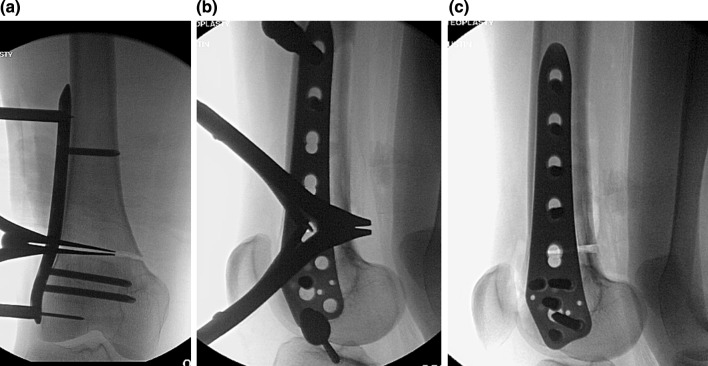

Fig. 3.

a An AP view of the posterior opening wedge osteotomy in patient 1 with the laminar spreader inserted centrally in the posterior cortex. Care is taken to avoid eccentric placement of the laminar spreader which could lead to unwanted varus–valgus deformity, b a lateral intraoperative view of the laminar spreader is seen holding the bony correction during plating, and c the final result of the posterior opening wedge correction after plating is seen on this lateral radiograph